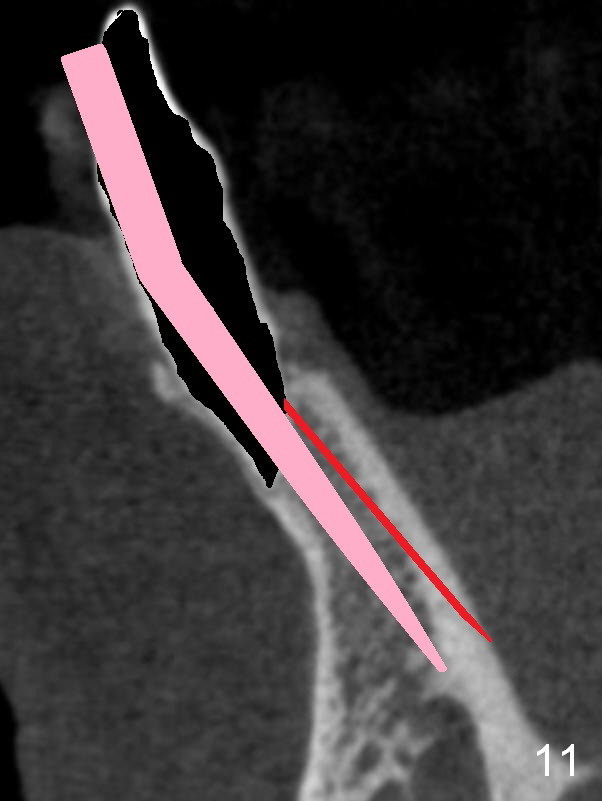

A 74-year-old man has several missing teeth (Fig.1). His 1st goal is to replace the lower left lateral incisor (Fig.2). The residual root has an apical lesion (Fig.3 *). To describe intraop findings, a CT image of a different patient is used (Fig.4 coronal section; B: buccal; L: lingual). After extraction, the buccal plate is found to be thin and low (Fig.5 arrowheads). A 1.5 mm pilot drill (Fig.6 red line) is used to initiate osteotomy in the lingual plate of the socket. Once the drill penetrates the lingual plate, the trajectory changes and the depth is 17 mm from the gingival margin (Fig.7). A PA is taken (Fig.8); it appears that the osteotomy can be extended more apically. When the pilot drill extends to 20 mm, there is sudden empty feeling. The lingual plate has perforated (Fig.9). A new osteotomy is established buccally (Fig.10 pink). To avoid buccal plate perforation, especially in the buccal undercut area (>), the coronal end of the drill has to be tilted buccally (<--). An angled abutment (3x20 mm, 15°) is placed (Fig.11,12). The abutment is modified (Fig.13,14) to accommodate an immediate provisional (Fig.15,16 P). Perio dressing is to be applied to prevent the bone graft from getting dislodged buccally (Fig.15). The dressing is in place 7 days postop (Fig.17).